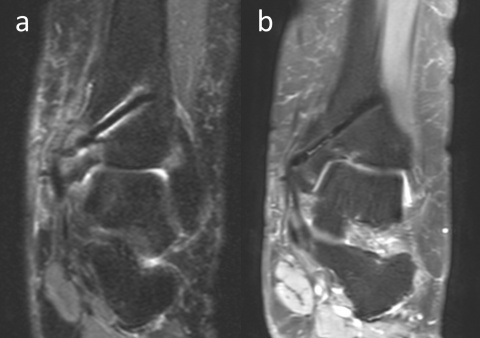

Als eines der Metalle aus der Gruppe IIa des Periodensystems hat Magnesium paramagnetische Eigenschaften. Frühere experimentelle Studien haben jedoch gezeigt, dass Magnesiumimplantate deutlich weniger Artefakte erzeugen als andere Metallimplantate (Abbildung 7). Sonnow et al. verglichen mithilfe einer 1,5 T MRT mit verschiedenen Sequenzen die Größe der Artefakte, die von Magnesium- und Titanschrauben in Hühnerknochen erzeugt wurden. Sie berichteten bzgl. Magnesiumimplantaten von einer signifikant geringeren Artefaktbildung gegenüber Titanschrauben (18). In ähnlicher Weise demonstrierten Filli et al. und Ernstberger et al. mit Implantaten auf Magnesiumbasis eine geringere Artefaktbildung in der MRT (19, 20). Diese Studien wurden allerdings nicht mit korrodierten Magnesiumimplantaten durchgeführt. Es liegt mit degradierten Implantaten im Menschen jedoch eine MRT-Studie vor, die drei Jahre nach Implantation durchgeführt wurde. Plaass et al. nahmen eine MRT-Evaluation an acht Patienten nach korrektiver Hallux valgus-Osteotomie vor und berichteten über eine lineare Hypointensität im Bereich des ehemaligen Implantatlagers ohne Metallartefakte (21). Diese Ergebnisse weisen darauf hin, dass die Menge der Artefakte während der Resorption des Implantats im Zeitverlauf abnimmt.

einer Innenknöchel-Osteotomie und Mosaikplastik unterzogen wurde. PD-gewichtete koronare

MRT-Aufnahmen in den Monaten 3 (a) und 13 (b) zeigen, dass die Artefakte im Laufe der Zeit

abnehmen.